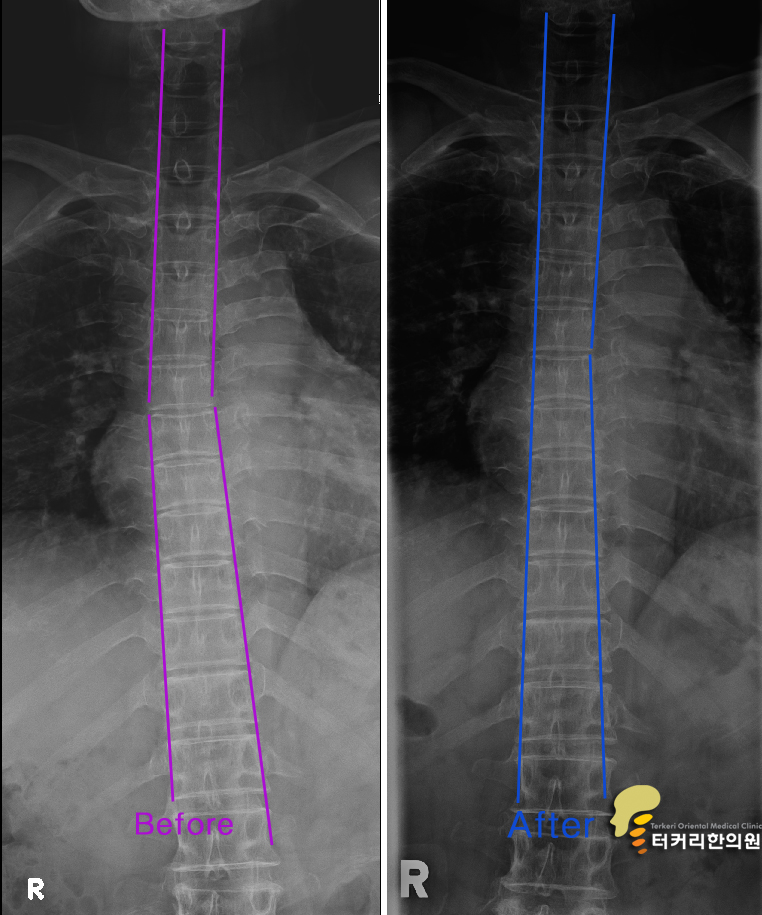

척추의 교정 전과 후 척추신경은 기차이고 척추는 기찻길입니다.

어느 한 위치에서 기찻길에 문제가 생기면 그 라인의 기차운행은 정지됩니다. 허리가 좁아졌다면 일자목이거나 휘어진 경추부터 C커브로 만들고 휘어진 척추도 바르게 교정을 해야 좁아진 허리 척추 간 간격이 순차적으로 벌어지게 되어 탈출된 디스크가 다시 척추사이로 들어올 수 있게 됩니다. 척추 라인이 정상으로 재조립이 되지 않고서 통증만 줄이는 치료는 매우 비과학적인 치료방법입니다.

쓰러지고 좁아진 집 기둥을 새것으로 인테리어를 하듯이 추간판탈출증, 요추협착증 환자도 경추가 C커브로 바뀌어야 하고 휘어진 등도 바르게 인테리어를 받아야 좁아진 목과 허리의 간격이 넓어져서 디스크 신경의 압박을 줄이는 바른 척추 기둥으로 바뀌게 됩니다. 그렇게 하고 난 후 다시 X-ray, MRI 검사를 받아서 치료 전과 후의 결과가 달라지게 나오면 정말 척추가 새롭게 인테리어 된 것을 확인할 수 있고 이것이 진짜 척추의 치료가 된 것입니다. 이런 척추의 교정은 턱관절교정이 반드시 필요하고 신도림동 터커리한의원에서 치료를 받을 수 있습니다.